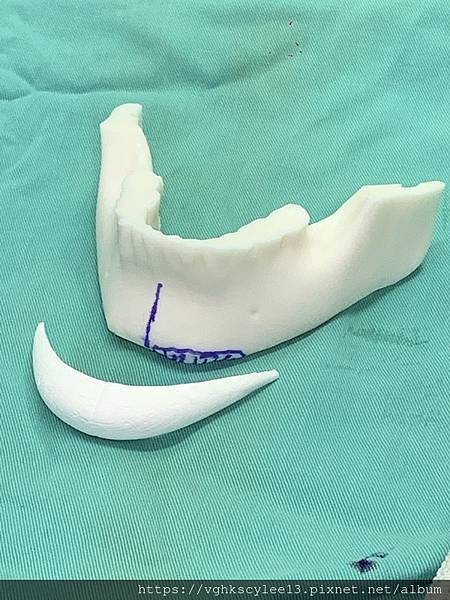

成型的下巴植體手術常遇到的就是不吻合臉型, 甚至可能因此歪斜(下圖),因此客製化假體相當重要避免術後不吻合或嘴邊斷層的嘎尬。

下圖重修歪斜下巴的過程:

李醫師針對重修下巴(上圖)的求美者有堅持:

1.務必3D電腦斷層評估與設計

2.配合工程師計算出落差數據

3.患者本人與照片分析評估及溝通

4.精準客製化適合假體![]()

下圖:不對稱下巴骨架,透過列印技術可以做出調整下巴歪斜的假體組合。

歪斜下巴調整性假體設計

下圖範例:歪斜不對稱下巴經3D導航客製化導航矯正性假體

下圖:或是以3D列印導板客製化下巴假體,以goretex材料按下巴導板來雕刻適合的形狀來訂製下巴,必要時把不規則的或不對稱骨頭磨平來改變術前傾斜。